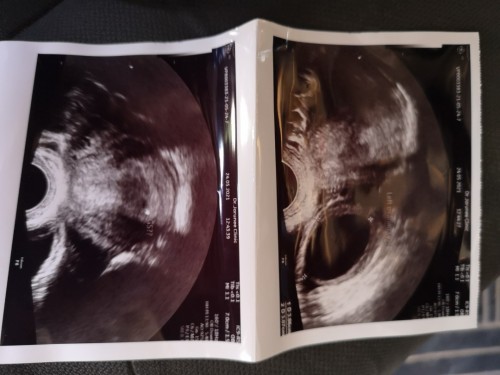

พอดีเราประจำเดือนขาดไป 3 วัน พอเราตรวจก็ขึ้น 2 ขีด ตรวจหลายอันมาก เพื่อความแน่ใจ และเราก็ลองคำนวณดูในแอป มันได้ 4 สัปดาห์ 6 วัน แล้วเราก็เลยตัดสินใจไปหาคุณหมอ คุณหมออัลตร้าซาวทางช่องคลอดให้ แล้วบอกว่ายังไม่เจอถุงตั้งครรภ์เลย อยากถามว่าเราไปหาหมอไวเกินไปไหม หรือว่าเราจะเป็นอะไรค่ะ ใครมีประสบการณ์ช่วยบอกหน่อยค่ะ พอดีท้องแรก เลยกังวลหน่อย😢 ขอบคุณค่ะ#ขอคำแนะนำหน่อยค่ะ